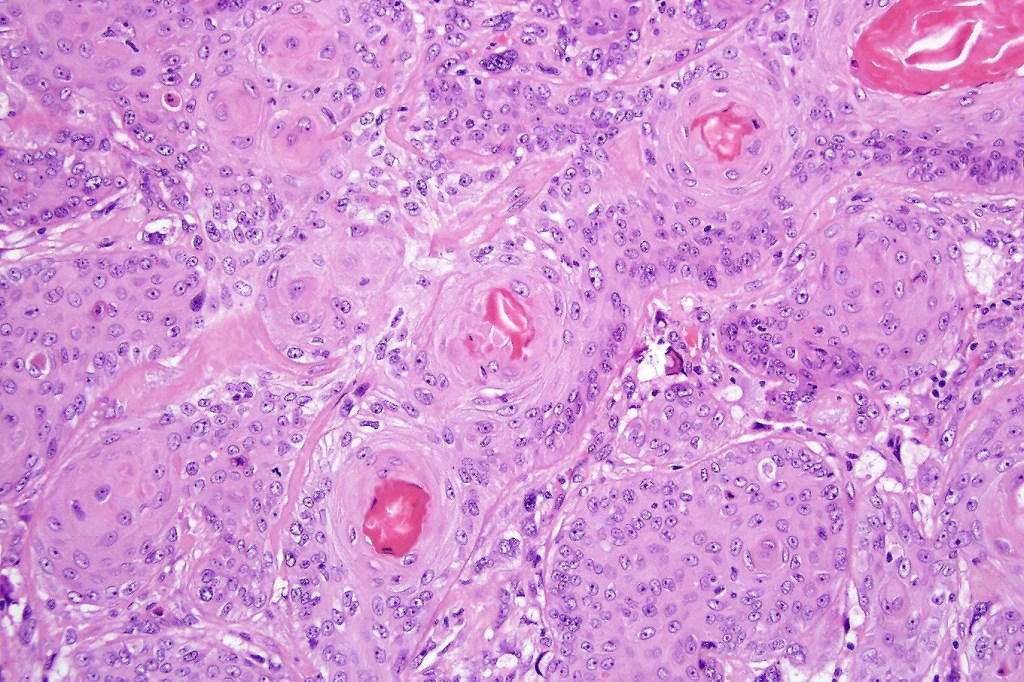

•Admixture of squamous carcinoma & pleomorphic spindled cell, osteoid, chondroid, MFH-like +/- osteoclast-like giant cells & rarely, smooth muscle, skeletal muscle, myofibroblastic or angiosarcomatous elements

•Epithelial component AE1/AE3, CK5/6 & p63 +ve;